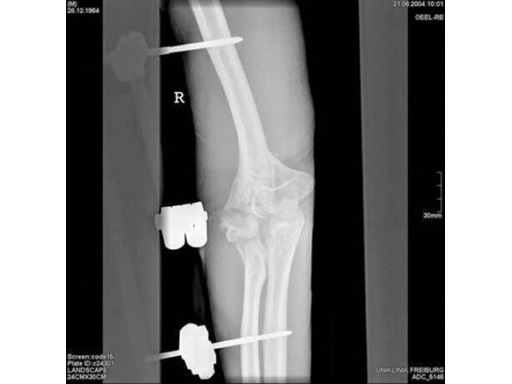

85-year-old woman, 13-C3, low supracondylar fracture treated with DHP.